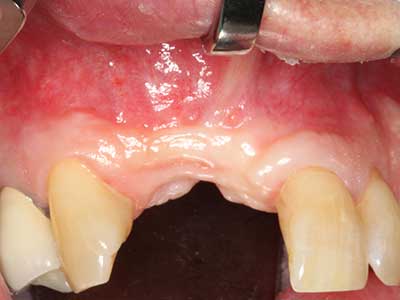

Fig. 13: l'irrigazione adeguata con l'osso residuo largo 4 mm è essenziale durante l'incisione ossea di questo paziente di 52 anni.

Fig. 14: posizionamento di quattro impianti RSX conici (BEGO Implant Systems, Brema).

Fig. 15: la radiografia dopo un follow up di un anno mostra condizioni stabili a livello osseo.

Fig. 16: anche le condizioni intra-orali sono stabili, con l'incorporazione degli impianti nella gengiva cheratinizzata.